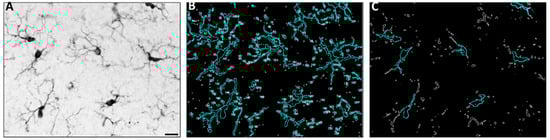

- Hovens, I.; Nyakas, C.; Schoemaker, R. A novel method for evaluating microglial activation using ionized calcium-binding adaptor protein-1 staining: Cell body to cell size ratio. Neuroimmunol. Neuroinflammation 2014, 1, 82. [Google Scholar] [CrossRef]

- Marshall, S.A.; McClain, J.A.; Wooden, J.I.; Nixon, K. Microglia Dystrophy Following Binge-Like Alcohol Exposure in Adolescent and Adult Male Rats. Front. Neuroanat. 2020, 14, 52. [Google Scholar] [CrossRef]